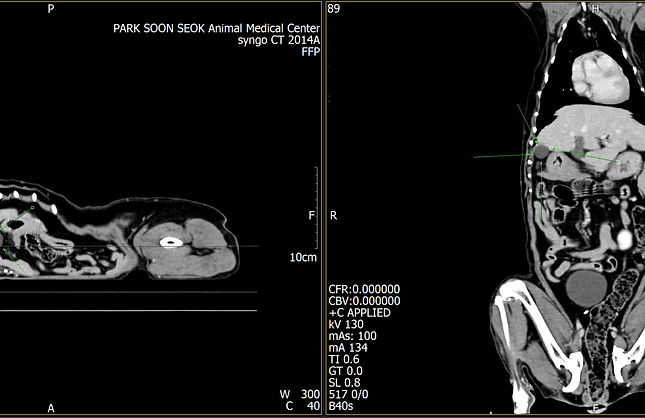

Siemens Somatom Emotion

CT

엑스레이를 이용해 mm 단위의 단면 이미지를 얻고, 이를 3D로 재구성하여 해부학적 구조를 정확히 평가하는 장비입니다. 16채널 멀티슬라이스 기술로 빠르고 정밀한 촬영을 10분 이내에 진행합니다.